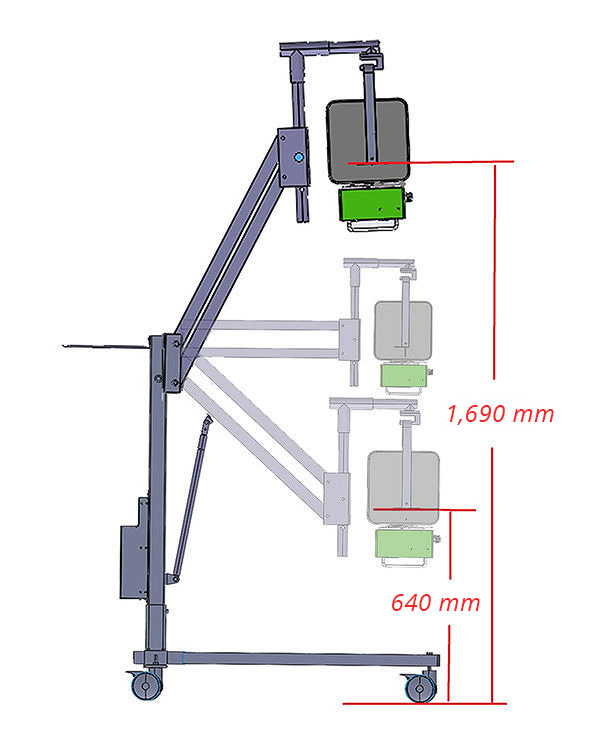

- 15cm Ground Clearance

- 120° Y-Axis Rotation

- 360° X-Axis Rotation

- Adjustable Z-Axis (640mm–1690mm)